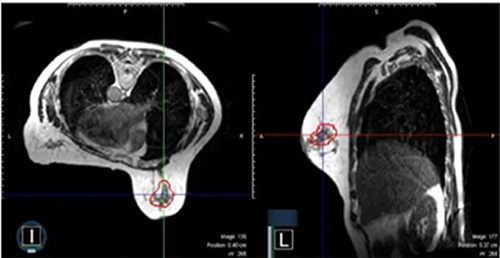

A representative surgical cavity target volume seen from an MRI image acquired on-table on the day of the radiation treatment. The MRI scans in both the axial and sagittal planes are shown. The surgical cavity is outlined in red. (Credit: John Ng, Ryan Pennell and Silvia Formenti. Front. Oncol., 23 November 2022)

PPI is the most advanced breast cancer radiotherapy technique available. By delivering the radiation treatment with MRI-guided precision and also using the prone position, this technology promises to further decrease the amount of normal breast tissue receiving radiation while targeting cancer cells. Currently PPI is available only at NewYork-Presbyterian/Weill Cornell Medicine, one of a limited number of institutions with an MRI linear accelerator, along with a long-standing expertise in breast cancer radiotherapy.

MRI offers significant advantages over the CT scans traditionally used for prone partial breast irradiation. “A CT scan sometimes is not very good at seeing where the tissue changes, meaning that if you look at the breast after surgery with a CT scan, you may not be able to precisely determine where the surgery occurred,” Dr. Ng explains. MRI is better at delineating soft tissue contrast and taking a more detailed picture of the surgical cavity. Also, doing a CT scan entails delivering very low but, nonetheless, safe doses of radiation to the entire body — an MRI scan does not.